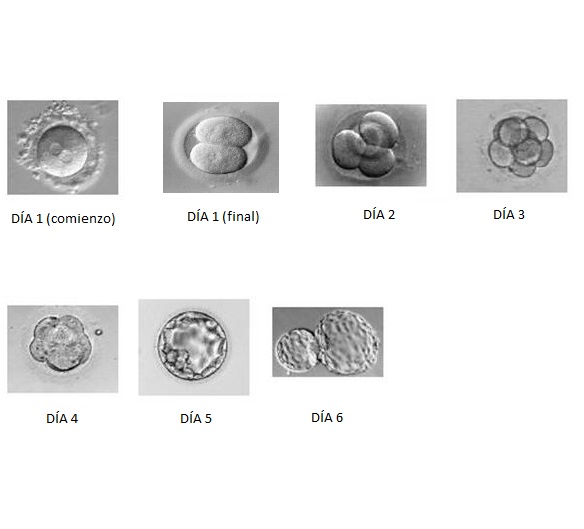

Anatomía del desarrollo

También llamada embriología, se encarga de estudiar el proceso del desarrollo embrionario de los seres vivos.

Para que un embrión se inicie, se necesita la fertilización que origina el cigoto. La embriología estudia todo ese proceso y el de la formación del embrión hasta su madurez.